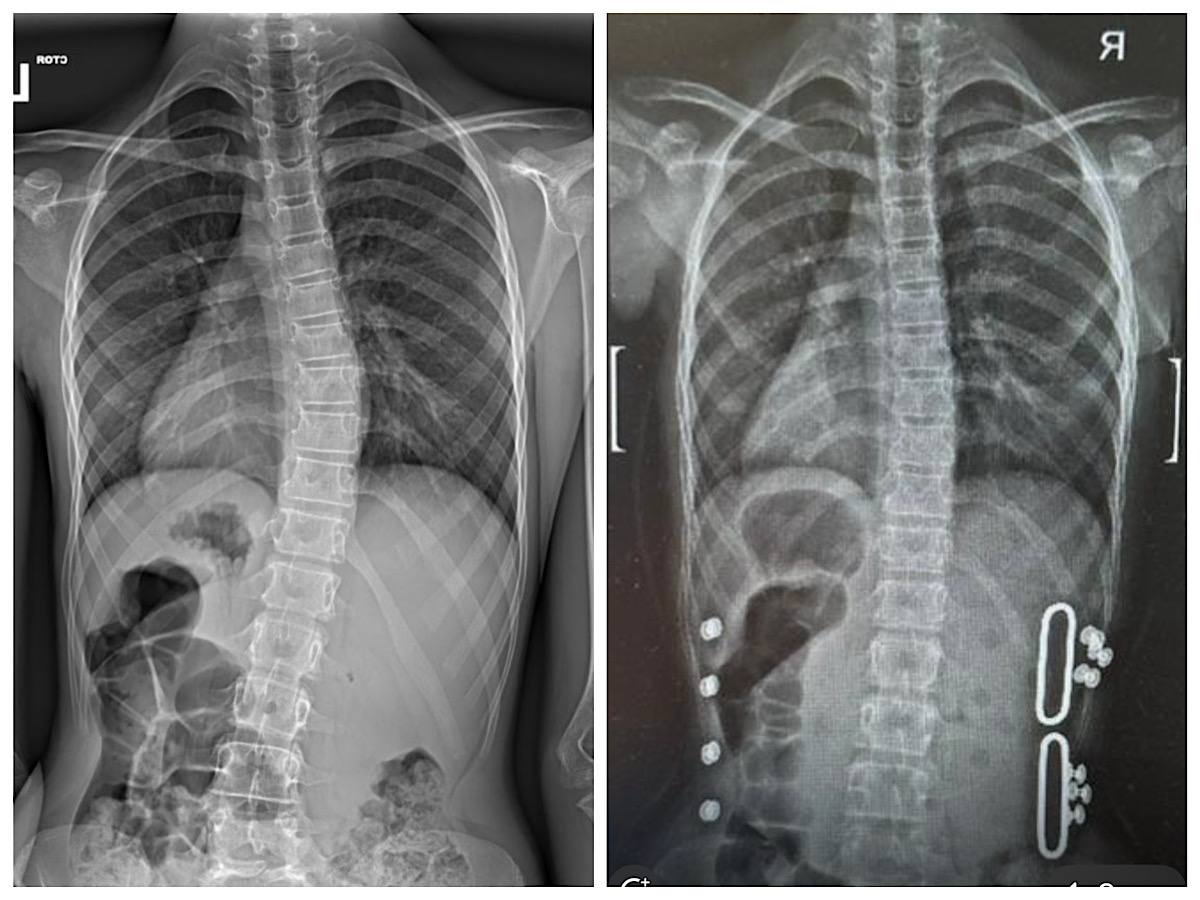

Корсет Шено

Вот так сработал корсет Шено за несколько месяцев ношения🔥🔥🔥 Плюс в комплексе девочка ходит ко мне на Шрот-терапию 2 раза в неделю. Результаты налицо!